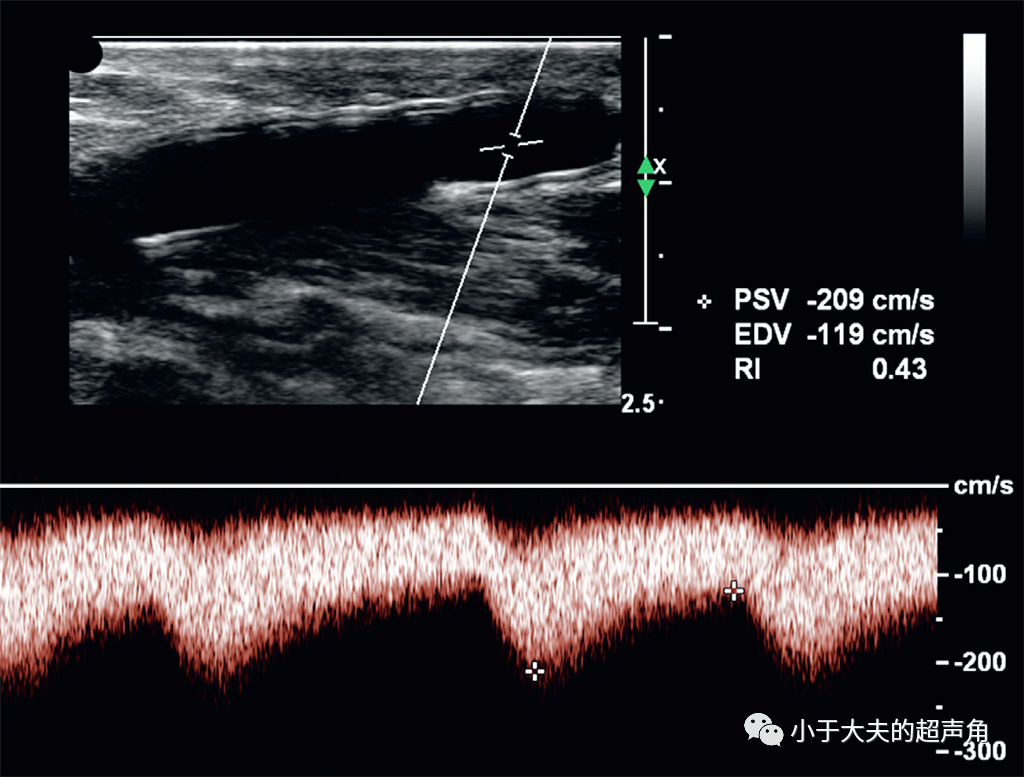

超声诊断动静脉瘘两例.----zengerya